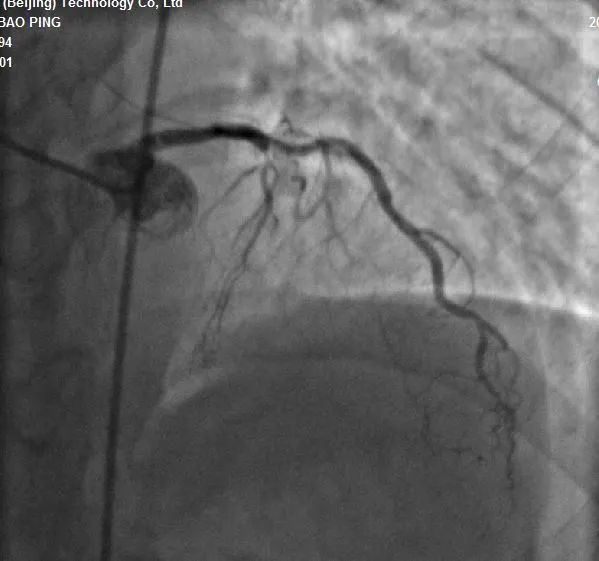

近日 长治二院心血管内科团队 成功完成 一例高难度 逆向CTO(冠状动脉慢性完全闭塞病变)介入手术 该项技术的成功突破 标志着医院心血管内科 冠脉介入技术跃 上了一个新的台阶 ...... 病例分析 手术现场 手术过程:7F LA1.0指引导管到位RCA开口,SionBlue(0.014”、0.5g)导丝送至后降支(PD3 )作为逆向导丝进入间隔支,以tip-injection技术进行间隔支超选择性造影,以明确逆向通路走形。逆行进入LAD中段,再次以tip-injection技术进行超选择性造影以明确LDA闭塞段以远情况,操纵导丝逆向行进至LAD中段闭塞段以远,尝试穿过闭塞段逆行到达LAD近段,推送逆向微导管通过闭塞段进入正向指引导管内,缓慢退出逆向系统至右冠内,逆向造影显示通路安全,撤出逆向系统。顺利预处理闭塞段病变后,于LAD近中段植入两枚支架,优化支架后,结果满意。 ▲术前造影结果 ▲术中逆向通道建立 ▲前降支CTO顺利开通 科室推荐 专家推荐 山西省心脏重症专业委员会常委、心律失常学组常委、介入学组常委。长治市心血管专业委员会、胸痛专业委员会及介入质控部副主任委员。 咨询热线 长治二院心血管内科 0355—3126031 冯翠萍主任 18603550120 姬小飞副主任 15635585652 李晋创医生 13546516641 供 稿丨冯翠萍 李晋创 编 辑丨卞 晨 审 核丨雷 赫